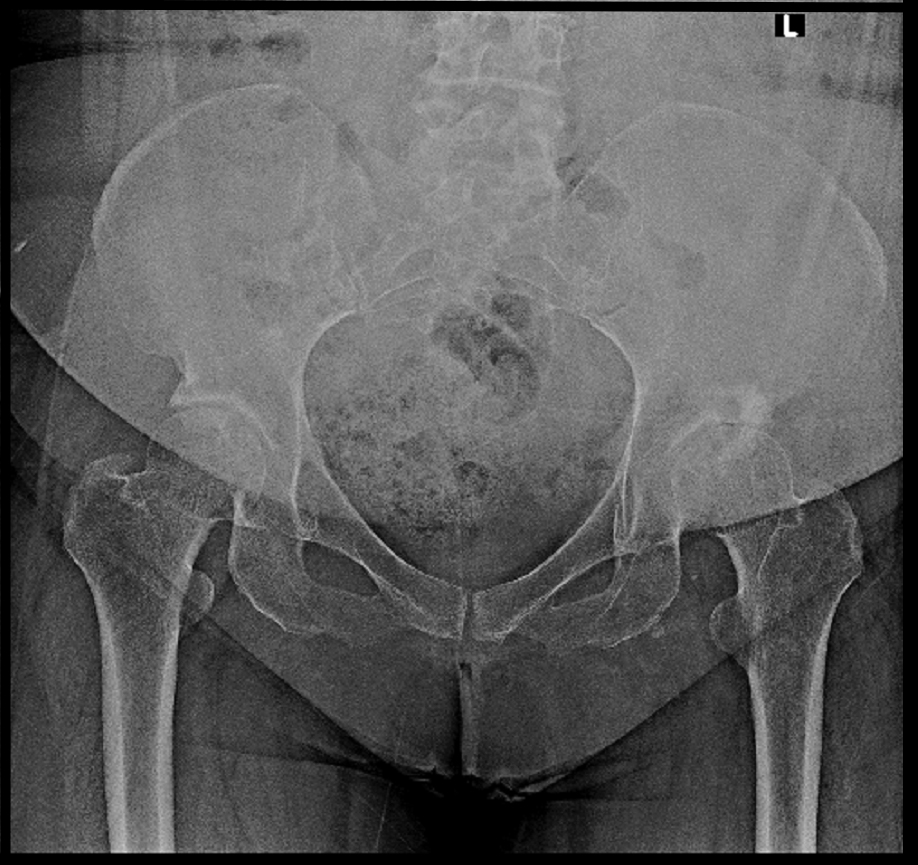

岡崎例 2.jpg

赤矢印が造影されたヒアルロン酸製剤となります。

8月にはヒアルロン酸製剤の関節内注入で以前より動きやすくなり、8㎏体重が減ったと述べていました。

X+2年12月の時点でもVAS2~3を維持しています。